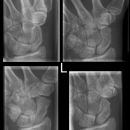

Handgelenk seitlich

Lagerung

Handgelenk, Unterarme, Ellenbogen (gebeugt) liegen mit der Kleinfingerseite streng seitlich auf. Handfläche hat leichte Retroflexion, d.h. der untere Handballen steht leicht vor. Daumen gestreckt über übrige Finger halten. Stellung durch Tasten im Handgelenk überprüfen.

Zentralstrahl

Senkrecht auf Handgelenk- und Filmmitte.

Anmerkung

Ulnar und Radius müssen distal übereinander projiziert werden. Os Scaphoideum und Os Lunatum liegen übereinander, ebenso die Mittelhandknochen, bei Verdacht auf Subluxation des Os Lunatums, Zusatzaufnahme in Flextion und Reflextion der Hand notwendig (Stressaufnahme).

Qualitätskriterien

Radius und Ulnar müssen deckungsgleich sein; Mittelhand, Handwurzelknochen und distaler Unterarm sollen abgebildet werden.